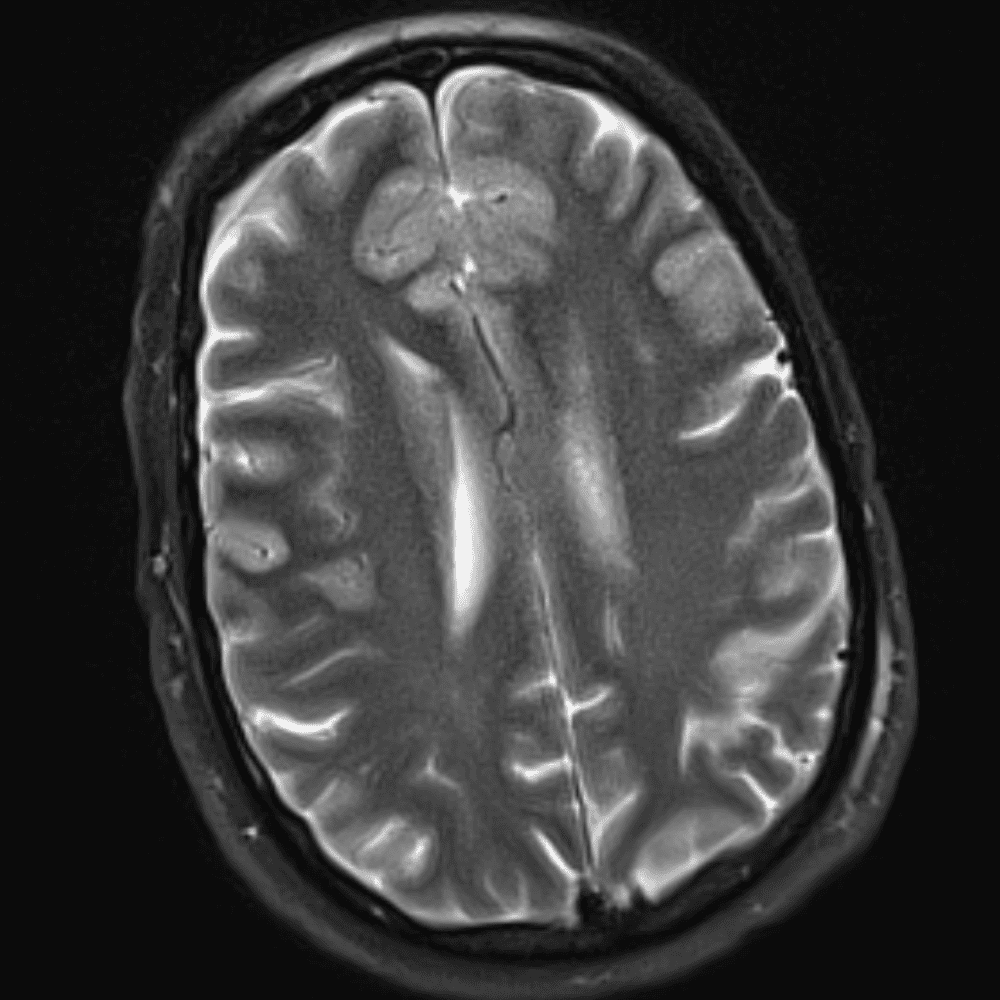

๋‹น์ง ์‹œ ํ”ํžˆ ๋ณผ ์ˆ˜ ์žˆ๋Š” ์‚ฌ๋ก€์˜ ์ „ํ˜•์ ์ธ ์˜ˆ๋ฅผ ํฌํ•จํ•ฉ๋‹ˆ๋‹ค.

39 ์‚ฌ๋ก€

์—ฐ์Šต

๋ฏธ๋ฌ˜ํ•˜๊ฑฐ๋‚˜ ์–ด๋ ค์šด ์‚ฌ๋ก€์™€ ์ผ๋ถ€ ์ •์ƒ ์‚ฌ๋ก€๋ฅผ ํฌํ•จํ•˜์—ฌ ๋‹น์ง์„ ์‹œ๋ฎฌ๋ ˆ์ด์…˜ํ•ฉ๋‹ˆ๋‹ค.

50 ์‚ฌ๋ก€